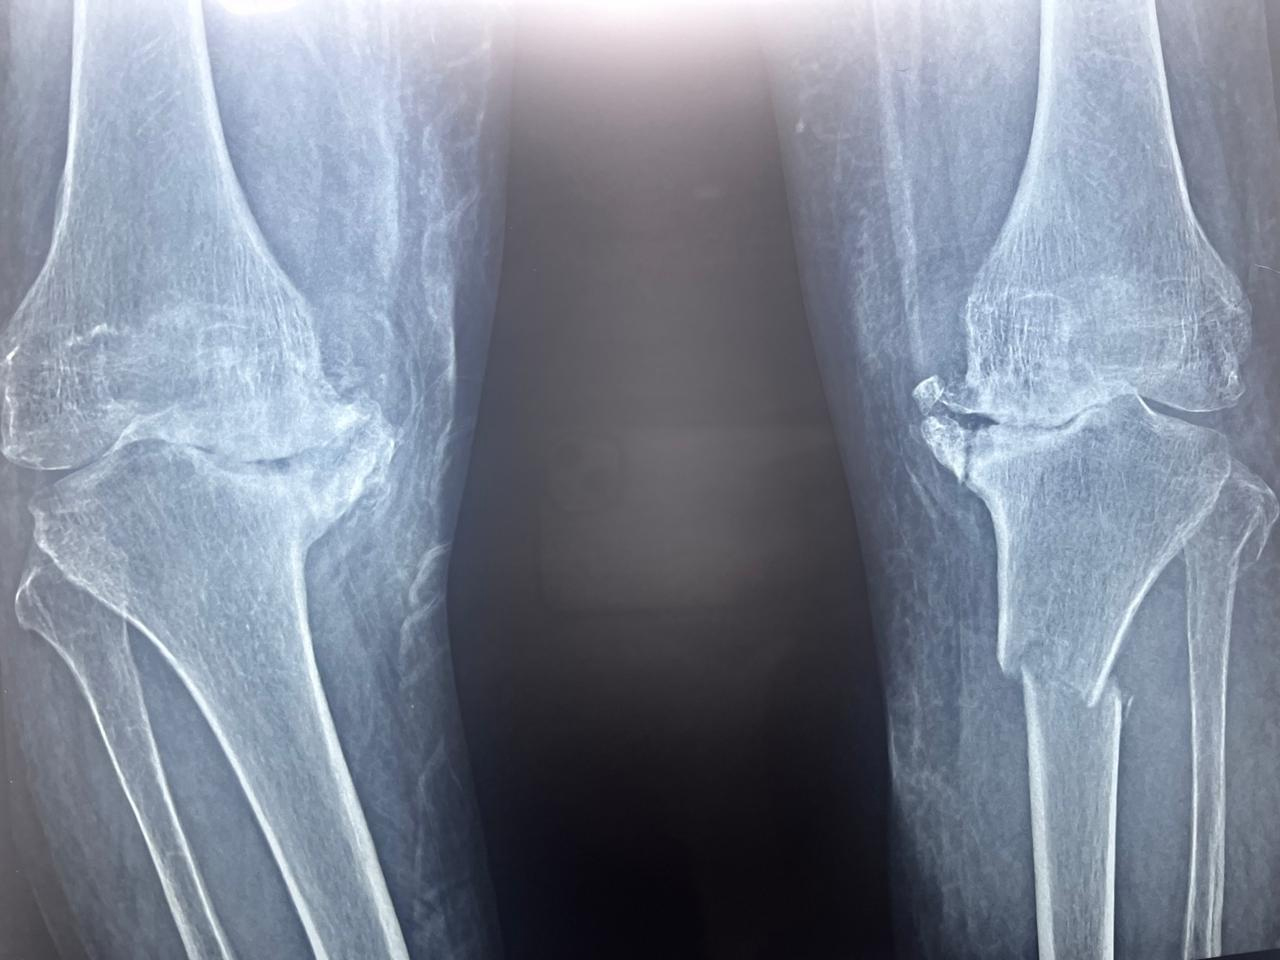

Talk on painfull knee in SL Raheja Hospital